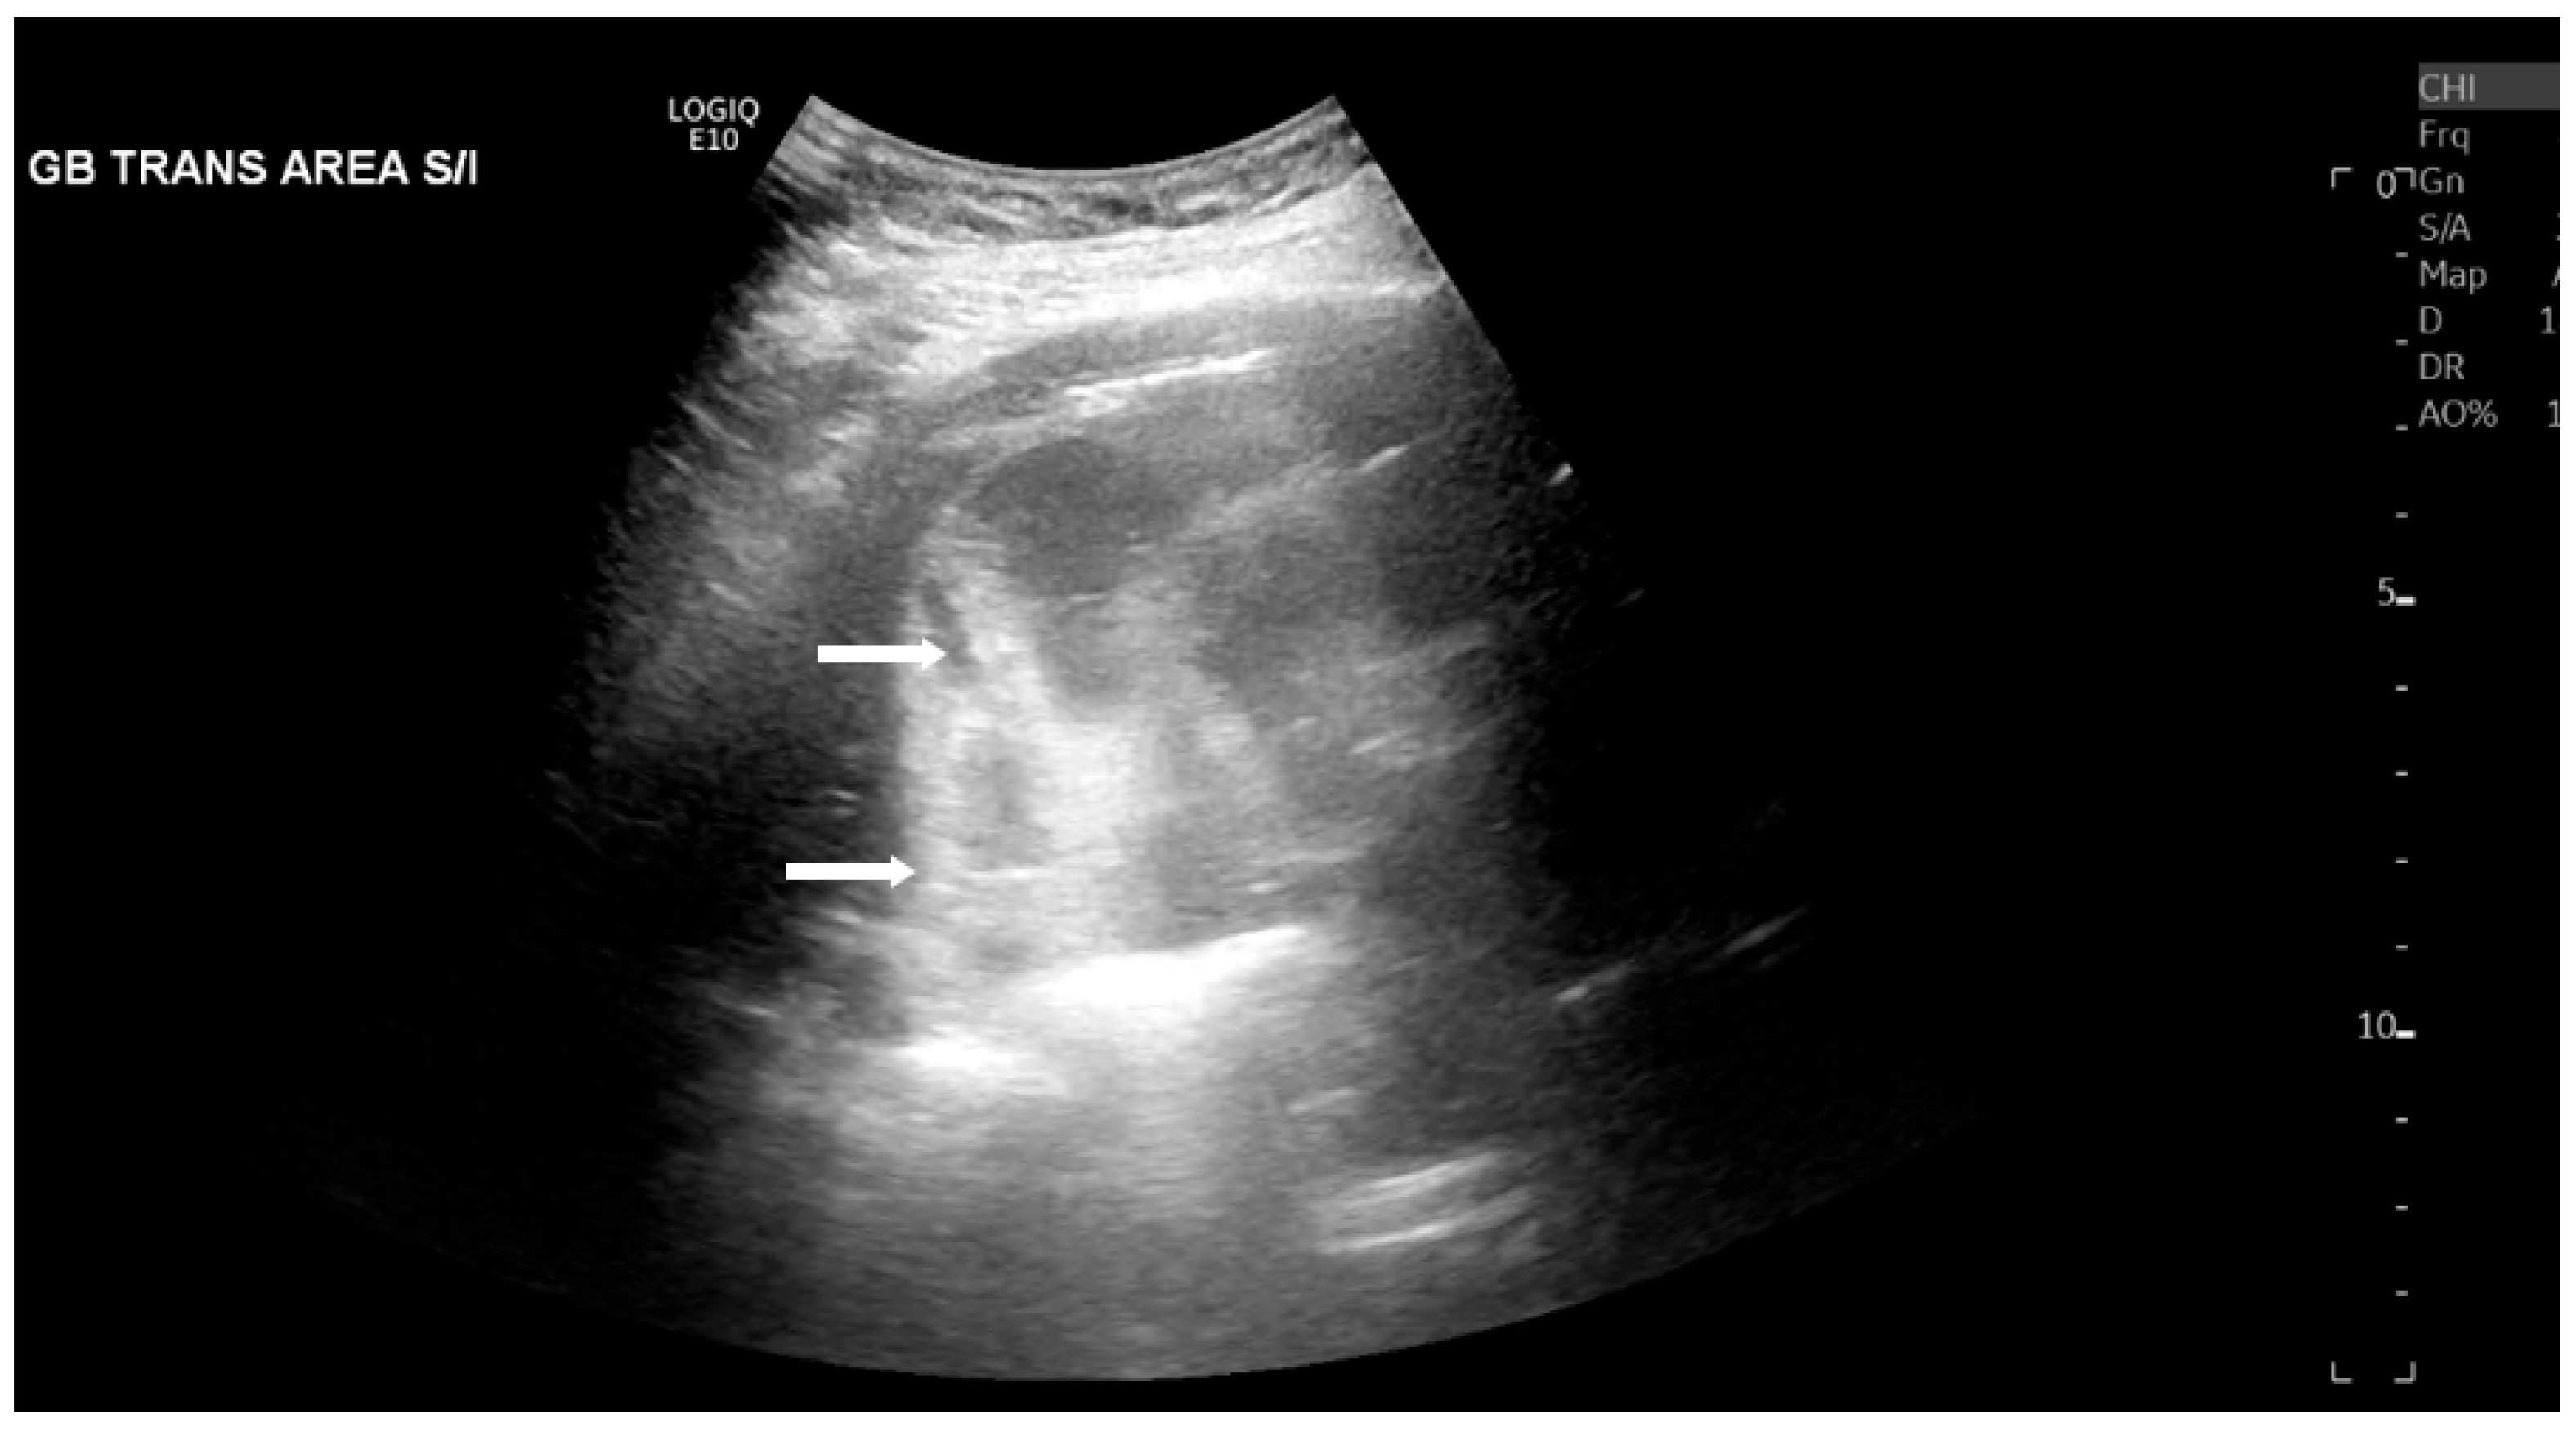

The most common sonographic finding of EC is the presence of gas within the gallbladder wall or lumen, which appears as highly echogenic foci accompanied by posterior dirty shadowing or reverberation artifacts, such as ring-down artifact, shown in Figure 1 and Figure 2. These artifacts are due to reflection and scattering of ultrasound waves by intraluminal gas. When the hyperechoic foci layer in the non-dependent portion of the gallbladder is present with low-level posterior shadowing, the appearance has been termed “the champagne sign” [16]. Furthermore, with changes in patient positioning, the gas may demonstrate mobility or layering on decubitus or upright imaging, aiding EC diagnosis. However, potential mimics of the visualized gas include gas secondary to recent instrumentation, biliary–enteric anastomoses, or sphincterotomy, which are important to consider clinically.

Additionally, the gallbladder wall may appear thickened (>3 mm) or irregular due to ischemic changes, inflammation, or gas dissection into the wall layers [13], as seen in Figure 3. Pericholecystic fluid and sludge may also be seen and are common but nonspecific findings.

Figure 1. Right upper quadrant ultrasound of a 63-year-old male diabetic patient with emphysematous cholecystitis. Posterior dirty shadowing (white arrows) due to gas within the gallbladder wall were demonstrated.